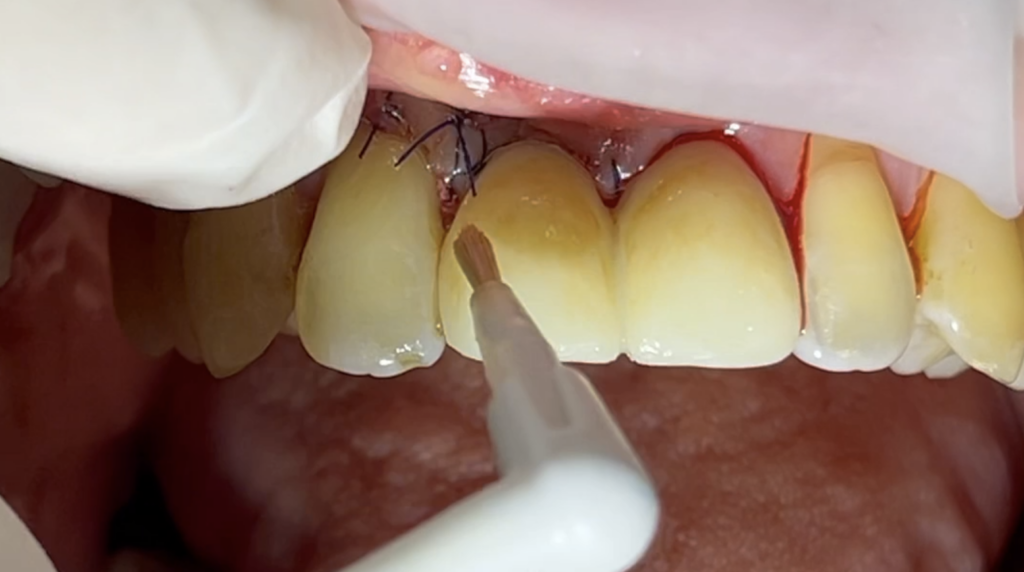

수술당일 임시치아를 끼웠고, 색상이 너무 하얗게 보여 스테인을 좀 해 드렸습니다.

임시치아를 주변색상와 맞추어 주는 과정

수술당일 임시치아를 끼운 상태

수술당일에 적용하는 임시치아는 충격을 받으면 안되기 때문에 아래앞니와 닿지 않도록 교합을 설정해 주었습니다.